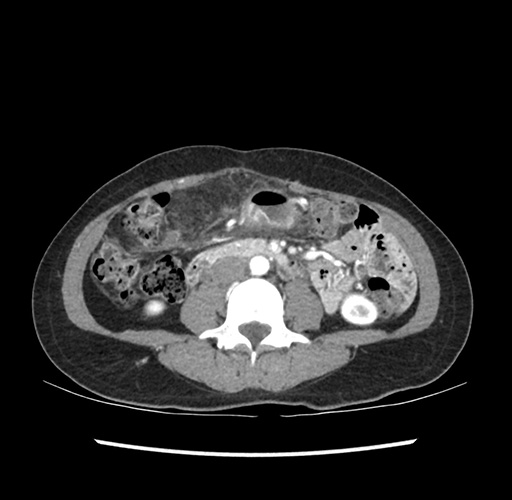

Imaging Analysis

Look through the patient's CT scan to identify any areas of concern for the necessary procedure.

Based on your CT findings, which issue(s) would give reason for "planned slowing down moment(s)" in this case?